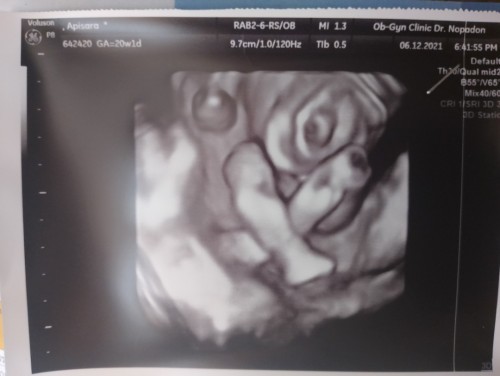

บ้านนี้ยิ้มโชว์ค่า ❤️